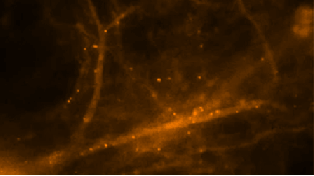

Este es tu Cerebro creando memorias

Los científicos de la Escuela de Medicina Albert Einstein de la Universidad Yeshiva han capturado cómo nuestro cerebro hace los recuerdos.